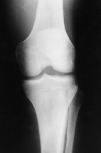

En la misma sala de urgencias se procedió a reducción cerrada, sintiéndose el chasquido, y se inmovilizó la rodilla durante tres semanas con yeso. Tras este período comienza movilización y carga progresiva de peso (Figs. 3 y 4).

Fig. 3.--Radiografía anteroposterior de rodilla en la que se aprecia el resultado tras la reducción cerrada con una imagen correcta de la articulación. Anteroposterior X-ray of the knee demonstrating the correct positioning of the joint after closed reduction.